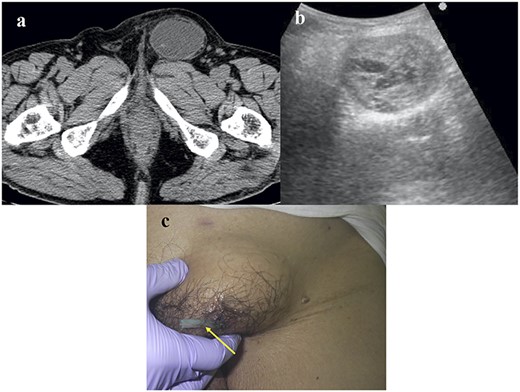

Two weeks later, he complained of an asymptomatic left inguinal bulging. Plain computed tomography (CT) revealed fluid retention with coating and no hernia recurrence (Fig. 1a). Ultrasound echography revealed a mosaic pattern within a 5.0 × 4.0 cm cyst (Fig. 1b). We considered the possibility of postoperative seroma; therefore, we decided to observe the patient for 1 month.

Images of the CEH. (a) Plain CT image. No hernia recurrence was observed and fluid collection was identified within the capsule. (b) Echography revealed a mosaic pattern. (c) A Penrose drain (arrow) was inserted into the CEH.

One month later, the cyst had not changed in size. The cyst was punctured, and a chocolate-like old hematoma (30 ml in volume) was aspirated. One week later, the temporally contrasting cyst had enlarged again. We inserted a Penrose drain into the cyst (Fig. 1c), which was also ineffective. Contrast-enhanced CT revealed findings similar to those of the plain CT performed for the diagnosis of fluid retention, with no extravasation. We decided to perform surgery because the conservative treatments trialed, including conservative observation, aspiration and drainage, had been unsuccessful.

The appearance of CEH is similar to that of seroma, which occasionally occurs following TEP, although the latter typically resolves without a specific procedure [11]. CT is useful for the discrimination of hernia recurrence and other pathologies. However, CT could not differentiate postoperative seroma from this rare entity of CEH. In contrast, magnetic resonance imaging is useful for diagnosing CEH [7, 8] but is often too expensive for this purpose. As shown in Fig. 1b, the echography findings of CEH, a mosaic pattern, differ from those of seroma, an echo-free pattern. Mosaic patterns likely reflect old hematomas with plasma from vessels. Because we did not observe the CEH following TEP, we first considered seroma and elected to observe the patient. After 1 month without observing the seroma, aspiration and drainage of the CEH were performed. At this point, CEH was considered because an old hematoma was evident.